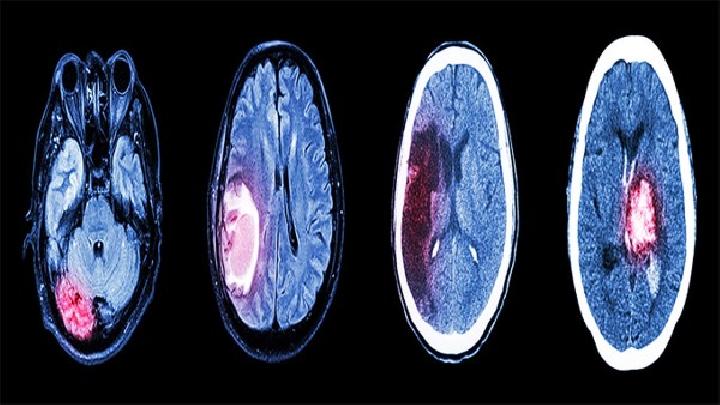

主要表现为头痛、呕吐、乳头水肿、瘫痪、部分运动性癫痫发作等,常伴有不同程度的意识障碍。虽然这些症状类似于颅内占位病变,但疾病紧急,病情迅速恶化,从疾病到症状顶部只有几个小时,大多数在一个月内;颅内压急剧增加,部分患者可迅速出现颅内压增加的风险;头部CT和MRI可见弥散性脑水肿和脑软化区,有助于识别脑瘤,但诊断有时依靠开颅检查或三维定向钻孔穿刺进行脑组织活检。